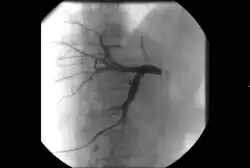

Angiography: Sometimes referred to as traditional angiography, catheter angiography or digital subtraction angiography (DSA). A small needle is inserted into a blood vessel, then exchanged for a catheter over a wire. The catheter is directed at the vessel to be studied, and contrast is directly injected to evaluate the lumen under video X-ray. This is an older technique than modern CT angiography or MR angiography, but provides unique advantages. With a catheter in place, provocative maneuvers can be performed such as breath holds or instillation of vasodilators, to evaluate a patient's blood flow dynamically. This can reproduce symptoms and identify functional abnormalities in a vessel that a static CT or MR imaging cannot.[80][81] Angiography provides the basis for all endovascular therapy.

Balloon angiography: The foundational IR procedure. Small balloons can be inflated inside a narrowed vessel to open it. These can then be safely deflated and removed. Some balloons have a specialized surface material, such as fine razor blades ("cutting balloons") to crack the plaque or instill a coating of medicine ("drug-coated balloon") that keeps the vessel open longer.